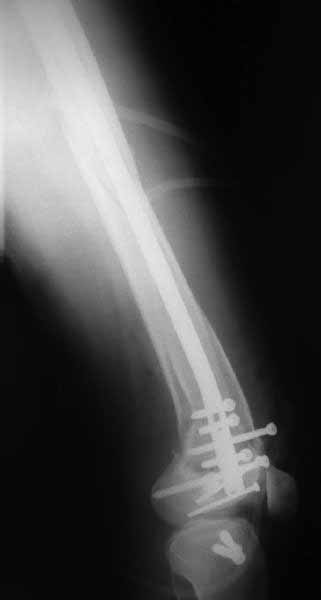

В приложении пример недавней операции, C3, открытая репозиция, фиксация мыщелков спицами и винтами, ретроградный синтез большеберцовым гвоздем 10,5 мм диаметром, винты 5 мм.

Позволю себе напомнить коллегам ещё раз, что являюсь сторонником антеградного остеосинтеза при переломах дистального эпиметафиза бедренной кости. Такая приверженность основана не на преимуществах внесуставного введения стержня или большем проценте положительных результатов. Она основана на возможности обеспечить блокирование на минимальном расстоянии от суставной поверхности в нескомпрометированной кости и, таким образом стабилизировать максимально низкие переломы. В приведенном Вами случае самый дистальный из блокирующих винтов проведен на расстоянии более 2 см от конца стержня. Из-за того, что к стержню присоединяется кондуктор, на стержне теряется 1-1,5 см его длины, где можно было разместить отверстия для блокирования. И что более важно, вместе с потерянной для этой цели длиной стержня утрачивается для размещения блокировочных винтов, пожалуй, самая ценная часть дистального эпиметафиза бедренной кости. Проблемы дистального блокирования в разных плоскостях, локализации точки ввода стержня при антеградном остеосинтезе – это всё решаемые технические проблемы. Но антеградный остеосинтез низких дистальных переломов бедра при адекватном блокировании в нескомпрометированной кости обеспечивает решение стратегической задачи – стабильный остеосинтез и возможность нагрузки.

Но практика показывает, что классификации существуют не зря, и стоит пользоваться ими, а не ориентироваться на абстрактные "максимально низкие переломы". Подавляющее большинство поступающих к нам больных с дистальными переломами - это C1 и С2. И показанный в прошлом сообщении гвоздик прекрасно справляется. Наверно, сгодятся и многие современные гвозди разных производителей, типа RAFN Synthes. А вот при настоящих C3 одним гвоздем не обойтись, нужны как минимум винты мимо, а то и введение на одном уровне нескольких винтов и/или спиц веером...

В приведенном Вами случае самый дистальный из блокирующих винтов проведен на расстоянии более 2 см от конца стержня.

На этом большеберцовом стержне центр ближайшего к кондуктору отверстия в 14 мм от конца. И пример был про то, что пластина тут, скорее всего, была бы не худшим выбором.